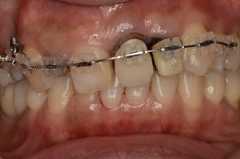

上下奥歯も含めた透明ブラケット矯正による治療例

上下すべての歯に透明なブラケットをつけて全体的な治療を行っています。